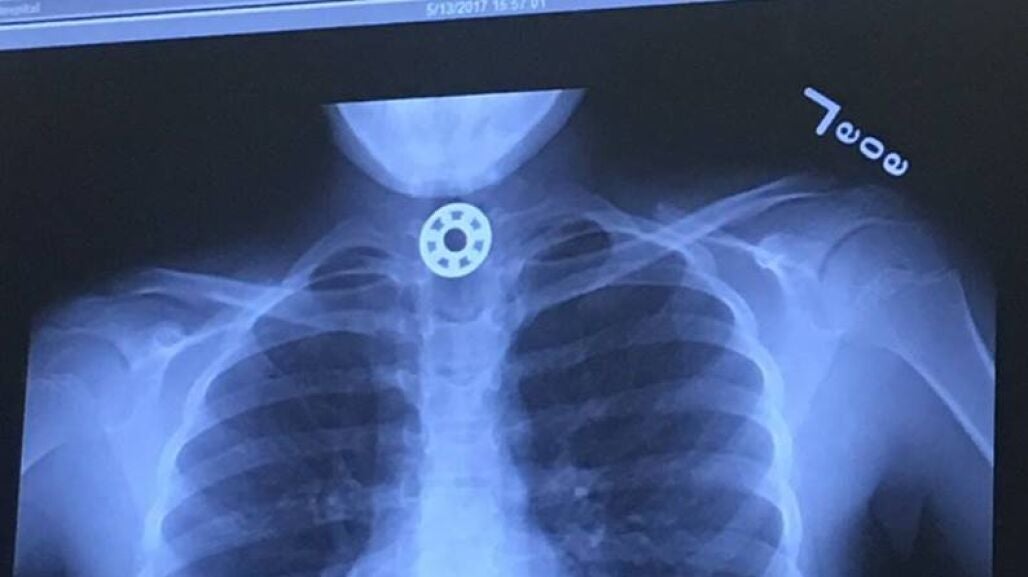

La madre, angustiada, trató de recibir ayuda médica rápidamente, pero los doctores no eran capaces de identificar dónde estaba el extraño objeto que la niña se había tragado. La pequeña fue trasladada al Hospital Infantil de Texas para que le realizaran una radiografía que mostró el juguete alojado en su esófago.